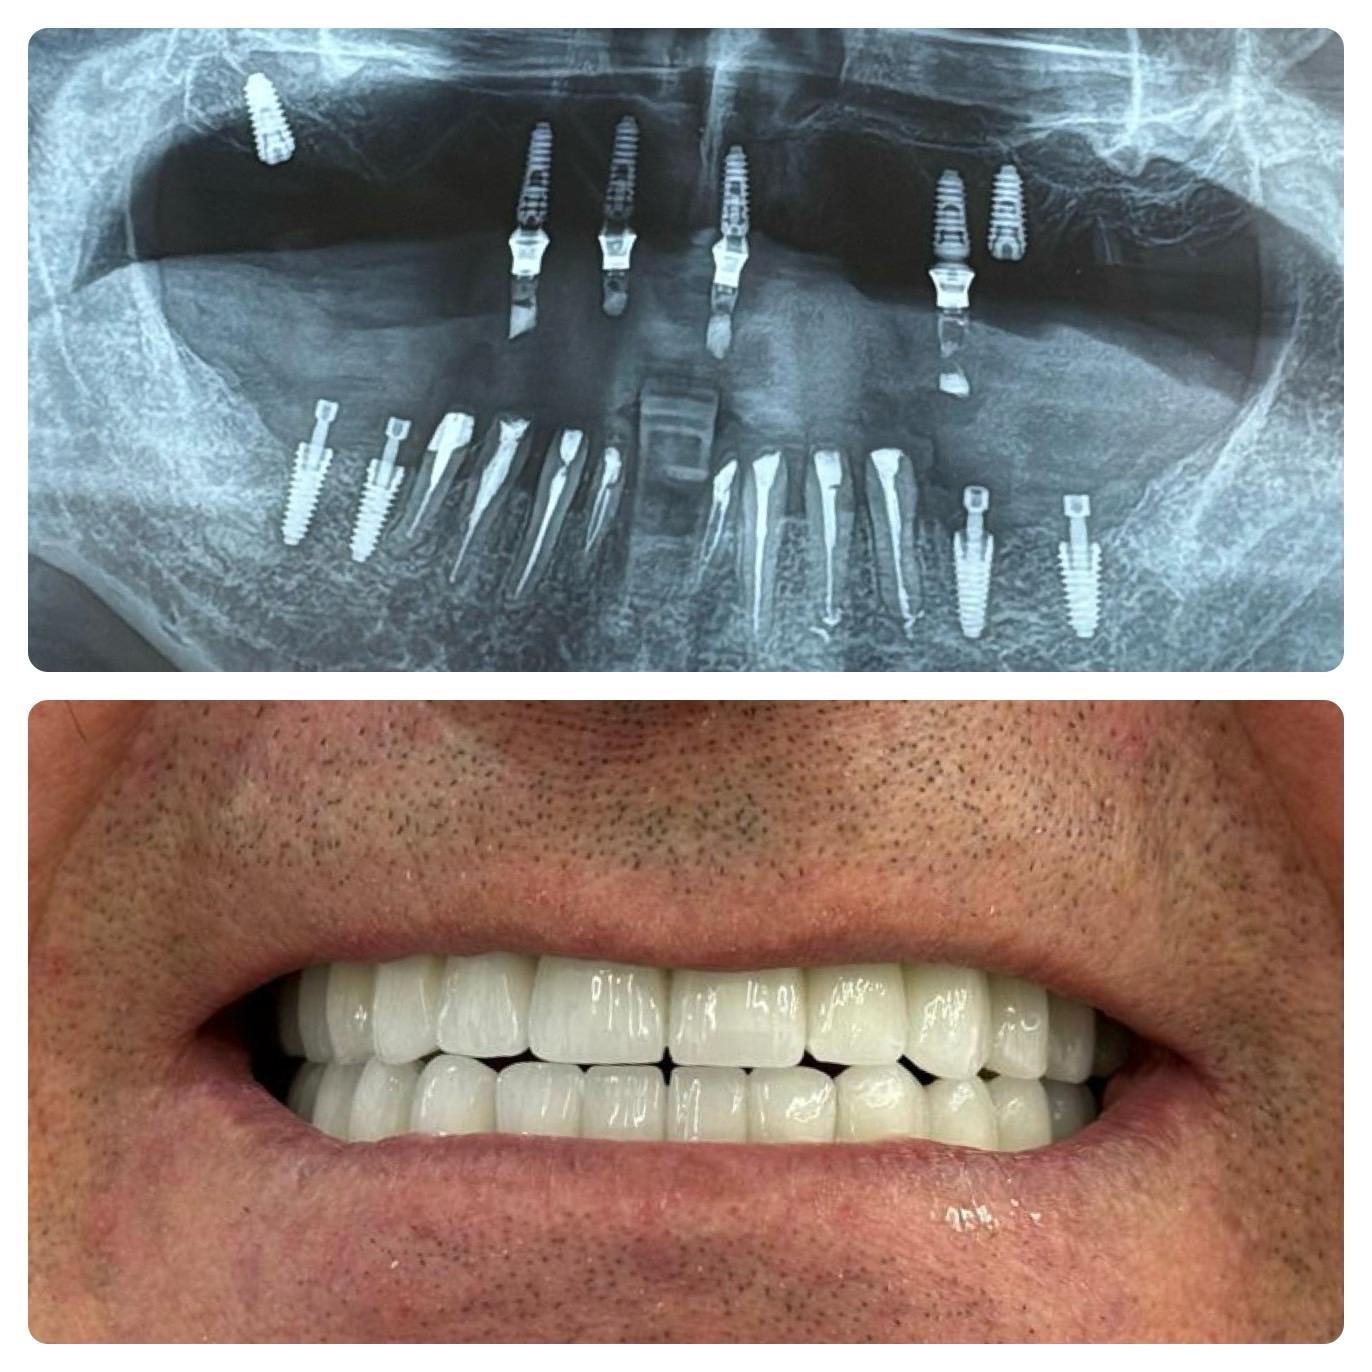

Gli impianti dentali rappresentano lo standard d’eccellenza per sostituire i denti mancanti, offrendo stabilità, durata e un aspetto e una sensazione naturali. Non migliorano solo l’estetica — ripristinano anche la capacità di masticare, preservano la struttura del viso e aiutano a prevenire la perdita ossea della mandibola. Per molti pazienti, gli impianti non sono solo cosmetici, ma essenziali per la salute orale a lungo termine e la fiducia complessiva.

Gli impianti proteggono l’osso mascellare, prevengono la perdita ossea e permettono ai pazienti di mangiare e parlare con piena fiducia — a differenza delle dentiere rimovibili. Diversamente dai ponti tradizionali, gli impianti non richiedono la limatura dei denti sani, contribuendo a preservare la struttura naturale dei denti. Gli impianti inoltre si percepiscono e funzionano come denti veri, offrendo comfort, stabilità e affidabilità che dentiere e ponti non possono eguagliare.

Si inizia con una consulenza e immagini 3D. Gli impianti vengono posizionati con precisione e restaurati con corone che appaiono e funzionano come denti naturali. L’intero processo è attentamente pianificato in fasi: valutazione, posizionamento dell’impianto, periodo di guarigione e restauro finale. Con le tecniche moderne, molte procedure sono minimamente invasive e spesso vengono fornite soluzioni temporanee, così da non rimanere mai senza sorriso durante il trattamento.